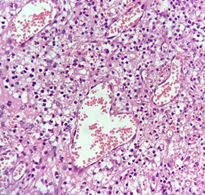

Figure 3c Sections show dilated and congested capillaries admixed with dense mixed inflammatory infiltrates, fibrosis, and foamy histiocytes (H and E, X40).